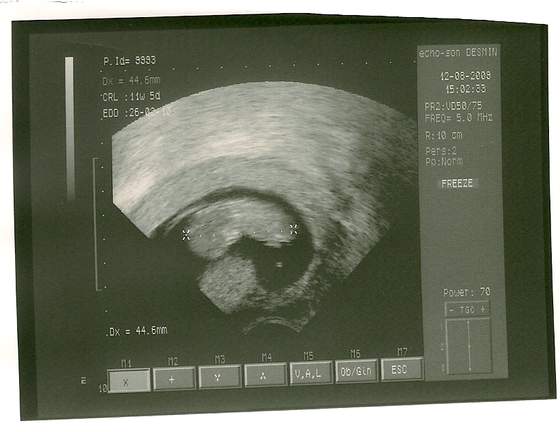

Mój Dziubasek

Agniesiak sliczne malenstwo. kurcze dobrze ze moge zobaczyc twoje malenstwo na zdjeciu bo moje zobacze dopiero za 9 tyg.Ale w tych Stanach torturuja. A nasze dzieci sa w podobnym wieku. Napisz ile centymetrow ma twoje malenstwo?